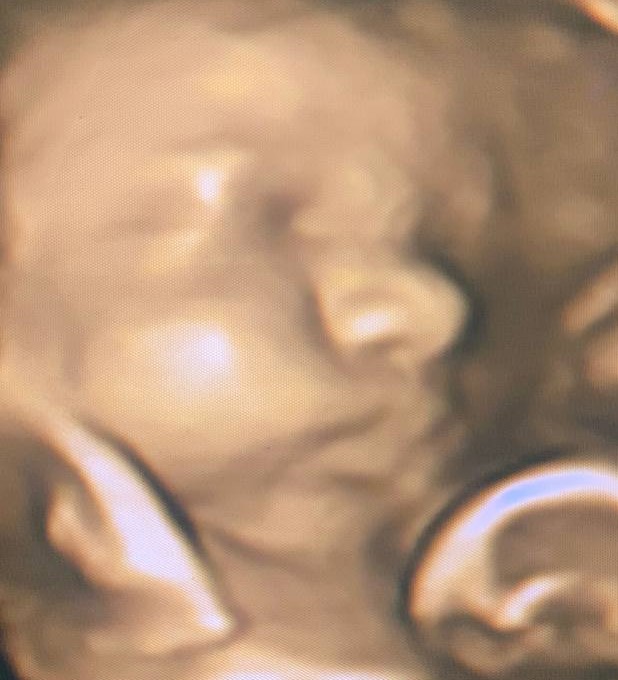

На що схожий малюк на 32-му тижні вагітності?

Малюк до 32-го тижня вагітності вже важить близько 1700 г, його зріст становить приблизно 42 см, а розміром він з ананас.

Очки малюка чітко реагують на світло і темряву, проте кольори малюк поки що не розрізняє. Цю здатність дитячі оченята отримають уже після народження. Своїми рухами крихітка щосили навчився сигналити про те, що йому подобається, а що ні. Наприклад, якщо ти знаходишся в дуже шумному місці, то він може почати «протестувати», активно штовхаючись ручками і ніжками. А якщо під час подібної активності заспівати йому колискову або погладити рукою, то малятко відразу ж заспокоюється.